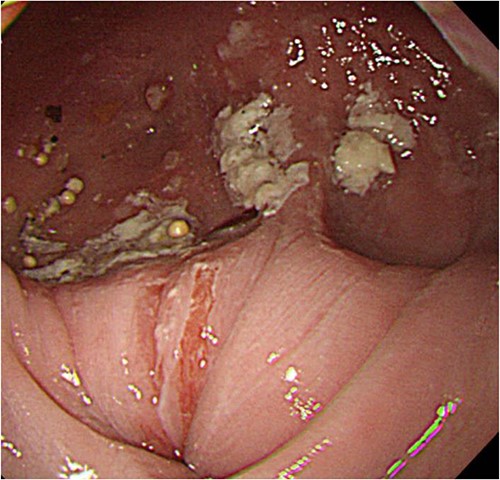

A 60-year-old female with dysphagia and vomiting visited the university hospital. In 2007, she underwent esophageal diverticulum resection (procedure unknown) with a diagnosis of an esophageal diverticulum, which subsequently recurred. In 2011, she underwent a transesophageal hiatus diverticulectomy and a fundoplication (Nissen procedure) at a local hospital. In 2013, dysphagia and vomiting appeared. The patient was diagnosed with recurrence and underwent balloon dilatation for follow-up. In 2015, the patient came to our hospital due to persistent symptoms. After one balloon dilation, the patient did not show any improvement and was referred for surgery. Esophageal fluoroscopy revealed a diverticulum 5 cm in size in the lower esophagus just above the eruption. There was no significant change in the diverticulum size before and after dilation (Figs 1 and 2). Gastrointestinal endoscopy revealed a diverticulum in the lower esophagus, with a residue accumulation (Fig. 3). The esophagus directly below the diverticulum was narrowed. The patient was diagnosed with recurrent lower esophageal diverticulum and underwent surgery.

Upper digestive tube endoscopy. The esophagus just below the diverticulum was stenotic, and there was residue accumulation in the diverticulum.